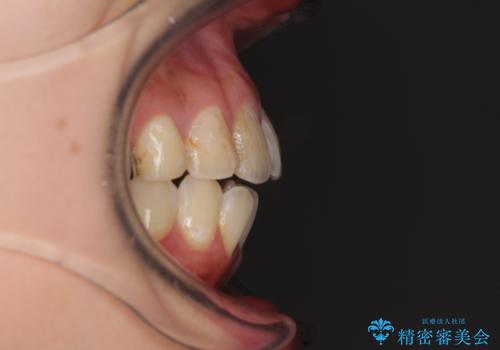

後戻りを治したい 骨格的なズレの大きい方のインビザライン矯正

- 中学生の時に矯正治療をしたものの、後戻りを気にして来院された患者様です。

骨格的に下顎が右側に変位しているため、左右の咬み合わせを理想的なものに改善することはできませんが、インビザラインにて歯列を整えることとしました。

骨格的なズレによる左右差は改善できませんでしたが、上下の正中を極力合わせるようにすることができました。